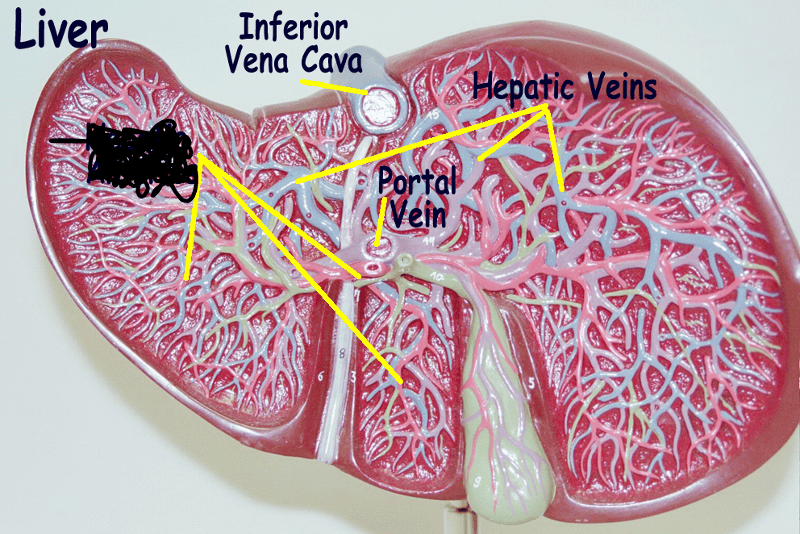

Hepatic portal vein

Liver

Renal artery/vein

Superior/inferior vena cava